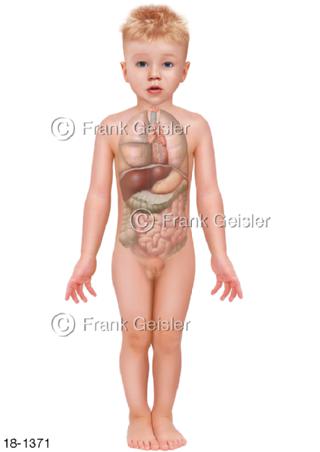

18-1371 Notfall Organe im Körper Kind Knabe